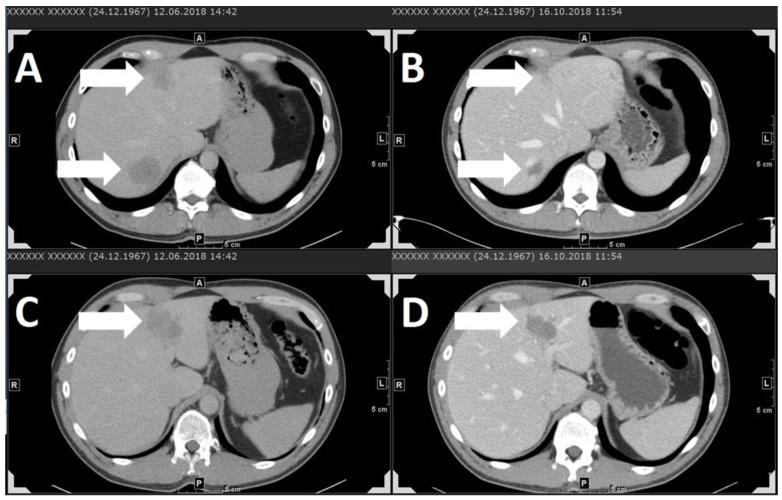

Uveal melanoma is the most common primary intraocular malignancy among adults. It is, nevertheless, a rare disease, with an incidence of approximately one case per 100,000 individuals per year in Europe. Approximately half of tumors will eventually metastasize, and the liver is the organ usually affected. No standard-of-care treatment exists for metastasized uveal melanoma. Chemotherapies or liver-directed treatments do not usually result in long-term tumor control. Immunotherapies are currently the most promising therapy option available.

Because few clinical trials have been conducted for metastasized uveal melanoma, no definitive treatment strategy exists for this rare disease. The outcomes of most immunotherapies are poor, especially compared with cutaneous melanoma. However, encouraging results have been found for some very recently investigated agents such as the bispecific tebentafusp, for which a remarkably increased one-year overall survival rate, and similarly increased disease control rate, were observed in early phase studies.